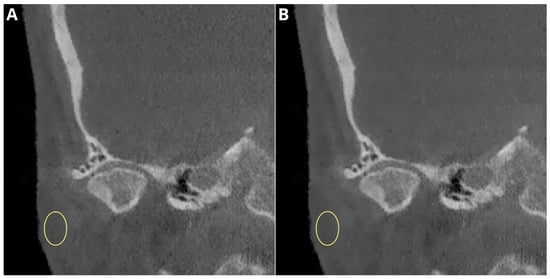

- flattening—the loss of the convex form of the articular surface;

- erosion and subchondral cysts—the loss of continuity in the cortical bone margins +/− cavities below the articular surface;

- osteophytes—marginal hypertrophy with sclerotic borders and the exophytic angular formation of the osseous tissue arising from the surface;

- subcortical sclerosis—an increase in the thickness of the cortical plate;

- condylar deformation—abnormal morphology of the condyle.